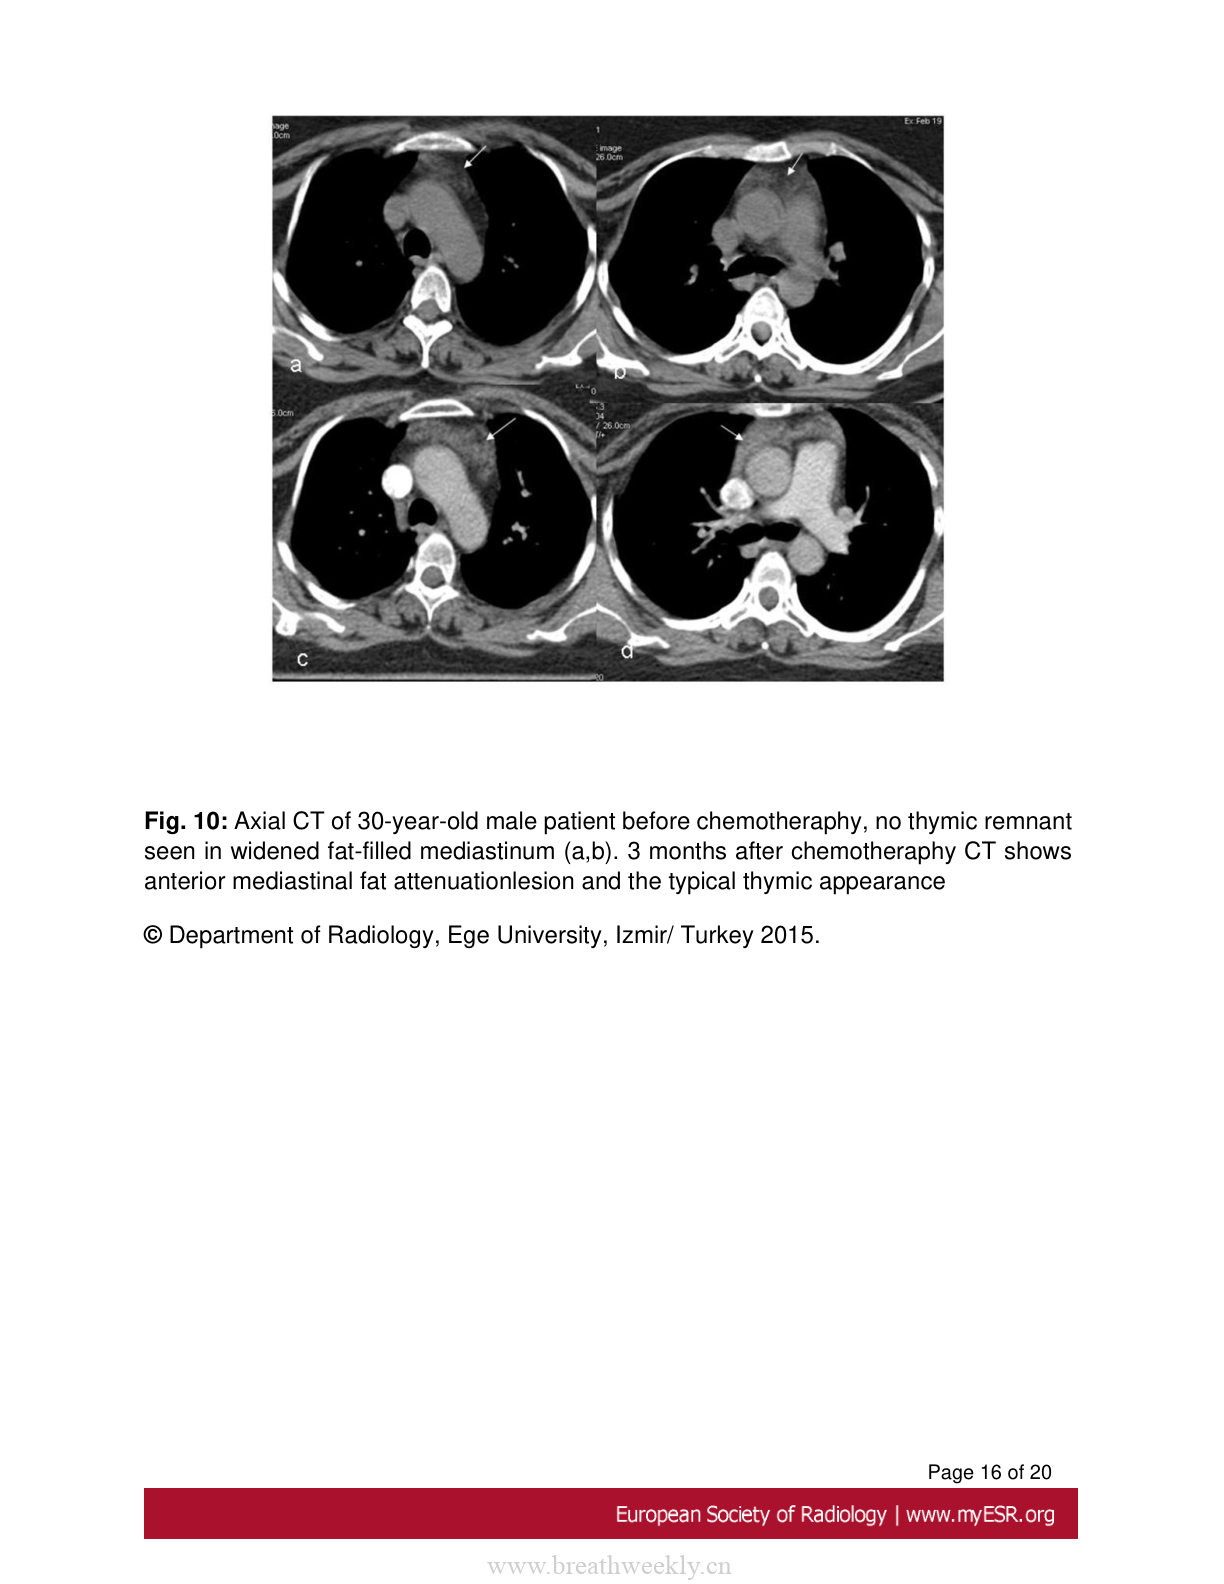

图10:反跳性胸腺增生

30岁男性患者化疗前后CT对比,显示前纵隔脂肪密度病变和典型胸腺表现。